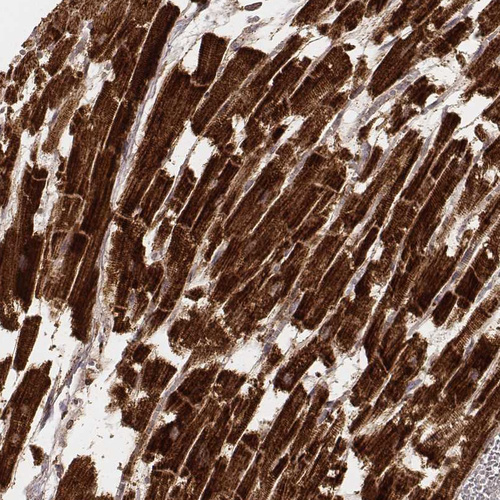

Immunohistochemistry analysis in human heart muscle and liver tissues using AMAb91009 antibody. Corresponding CS RNA-seq data are presented for the same tissues.